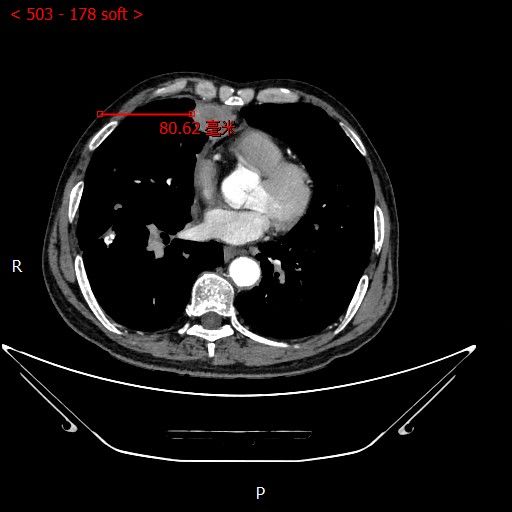

术中影像

男性患者,68岁,检查发现右肺中叶肿块,大小约3.5cm×2.4cm,因患者有慢性支气管炎、肺气肿、肺大泡,基础病较多,无法耐受常规外科手术治疗;经与患者本人及家属多次沟通。血管介入科团队根据患者具体情况决定对该患者施行CT引导下肺肿瘤射频消融术。经全科术前讨论:肿瘤位置毗邻心脏、纵膈、胸膜多处重要器官,手术要求穿刺精准,消融位置精确,尽量避免恶性心率失常,心脏包膜、胸膜、纵膈损伤。经过前期的精心术前准备,2023年7月18日,在血管介入科团队和CT室默契配合下,此次射频消融手术顺利完成。手术全过程仅用时约40分钟,其中消融时间约5分钟。CT观察下见肿瘤形变,周围肺组织呈现“晕”征,提示本次消融范围基本覆盖全肿瘤。术中患者无疼痛并且未产生并发症。本次手术达到杀死肿瘤细胞的同时,最大限度的减少创伤、保留肺组织。